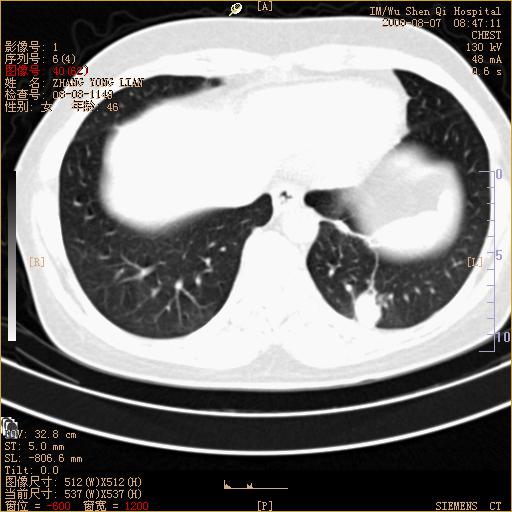

标题: CT15050:女,46岁,咳嗽胸痛一月余 [打印本页]

纵隔窗没发全,左下肺近胸膜处结节。有长毛刺,纵隔淋巴结增大,不排除恶性病变。

考虑肺癌

考虑左肺下叶后基底段周围型肺癌伴纵隔淋巴结转移可能性大。

左下肺ca并纵隔及左肺门区淋巴结转移。

脾脏低密度结节转移不排除。

1)考虑左肺下叶后基底段周围型肺癌伴纵隔淋巴结转移。2)脾内低密度灶,性质待定;不排除转移瘤可能。

考虑左肺下叶后基底段周围型肺癌伴纵隔及肺门淋巴转移。